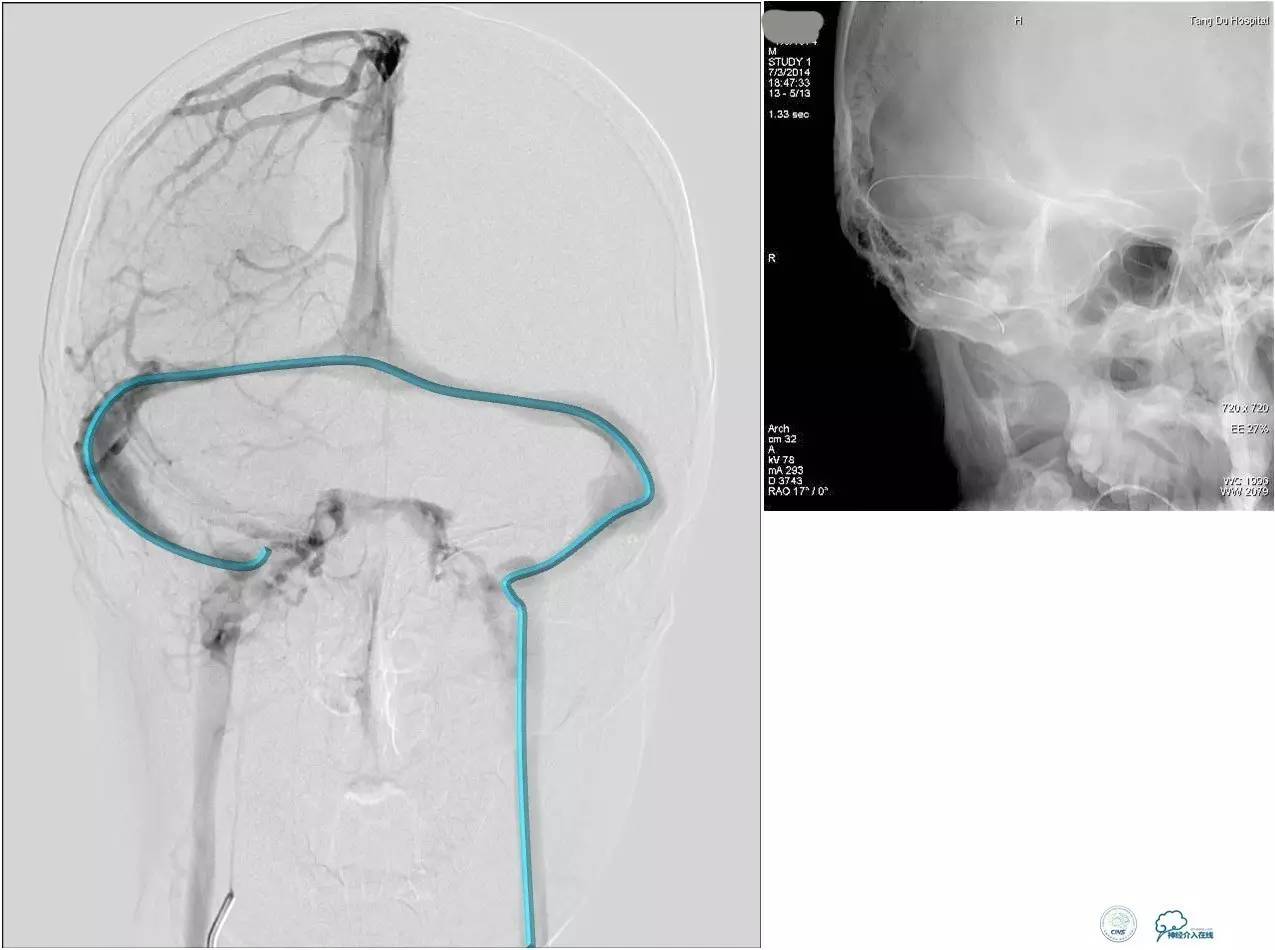

脑膜后动脉供血的小脑幕的瘘。

颈内不参与供血。

大脑后动脉有细小分支供血。

Sceptor球囊无法到达瘘口位置,放在主干内,充盈球囊后把动脉血管床内血液冲洗干净,形成楔入效果。